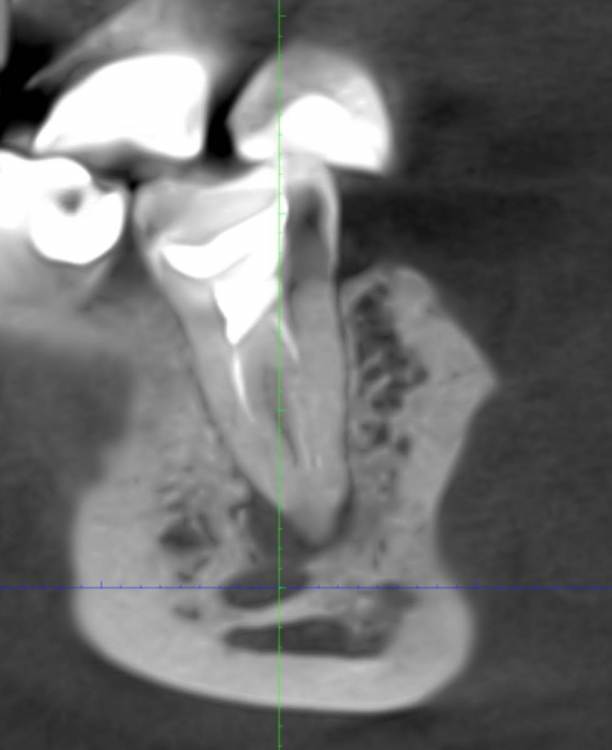

red_butler Опубликовано 10 февраля, 2023 Поделиться Опубликовано 10 февраля, 2023 Здравствуйте, все "мертвые" зубы нужно протезировать. А именно 1.2 13 1.4 1.6 1.7 2.4 2.5 2.7 3.5 3.6 4.5 4.6 4.7. Кроме этого требуется повторное лечение корневых каналов зубов 1.7 1.6 1.2 3.5 4.7. Лечение кариеса 3.7 По хорошему нужно сделать Кт. Вам нужен хороший ортопед. 1 1 Ссылка на комментарий

DoctorT Опубликовано 11 февраля, 2023 Поделиться Опубликовано 11 февраля, 2023 Нужно обратить внимание на состояние суставов (ВНЧС), что то мне подсказывает, что есть патологическая стираемость. Мое мнение: 1. КТ ВНЧС, в идеале МРТ ВНЧС. Для диагностики состояния суставов. 2. Санация полости рта. 3. Сплинт терапия (каппы) 4. Скорее всего, тотальное протезирование. 1 Ссылка на комментарий

safroxa Опубликовано 17 февраля, 2023 Автор Поделиться Опубликовано 17 февраля, 2023 Уважаемые доктора, сделала КТ. Прошу вас, пожалуйста..."палехчи") А если серьезно, то хотелось бы узнать, есть ли еще моменты на которые нужно обратить внимание? https://disk.yandex.ru/d/4koSWxtzJ8DNSg Спасибо за ответы. Ссылка на комментарий